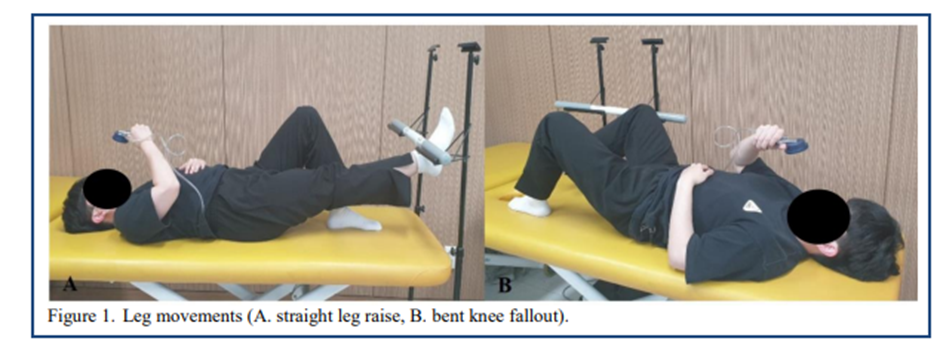

2020년도 연구논문에서는 다리의 무릎을 펴고 신전하는 Active Leg Raise(SLR)동작과

무릎을 구부리고 다리를 거상시키는 Bent Knee Fall out(KFO)동작수행시

Abdominal Hollowing과 Abdominal Bracing 그리고 휴식시를 비교한 논문연구를

언급해보려고합니다.

이 연구에서는 Abdominal Bracing방법이 Abdominal Hollowing방법보다 다리

신전거상(SLR)동작 수행시에 골반의 회전각도가 더 줄어들었다고 언급하고 있습니다.